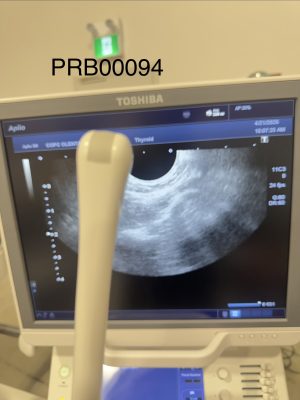

Product Description

Toshiba PVT-781VTE Endocavitary Probe Probe 2016

Description

MODEL PVT-781VTE